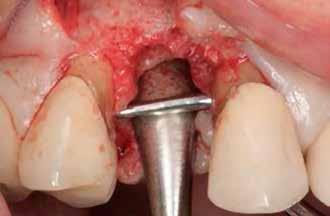

A 61 éves női páciens a reménytelen prognózisú jobb felső első kisőrlője miatt kereste fel klinikánkat. Kezelési tervében a 1.4 fog eltávolítását és megfelelő implant-protetikai ellátá-

sát javasoltuk. Jelen esetben szükség volt kiegészítő vertikális csontaugmentációra, amelyet az ún. hangár technikával, kizárólag saját csont felhasználásával végeztünk. Csont graftot a mandibula retromoláris régiójából nyertünk, szemilunáris a technika (SLT, semi-lunar technique) és az Easy Bone Collector segítségével. A hangár technika lehetővé teszi, hogy az implantátumot vertikális augmentációval egyidejűleg, az okkluzálisan rögzített csontlemezen keresztül helyezzük be. A módszer a repülőgéphangárról kapta a nevét, amelyet kimagasló szilárdság és íves boltozat jellemez.

3. ábra: Intraorális kiindulási állapot. – 4. ábra: A terület intraorális nézetből. 5. ábra: A lebenyes feltárást követően laterális és vertikális csonthiány látszik a 1.4 területén. – 6. ábra: Az Easy Bone Collector egy egyedi műszer, amely trepánfúrót, belső hűtést, kerámia csapágyakat és integrált lágyrészvédelmet tartalmaz. Mindez megkönnyíti a csontlemezek eltávolítását. – 7. ábra: A semilunaris technika és az Easy Bone Collector együttes alkalmazása több kortikális csontlemez kinyerését teszi lehetővé a retromoláris régióból.

Javasolt, hogy a lehető legpontosabban ragaszkodjunk a hangár technika műtéti protokolljához. Miután a csontlemezeket oszteoszintézis csavarokkal rögzítettük, az okkluzális csontlemezt egy trepán fúróval átfúrjuk (lehetőleg az implantátum átmérőjével megegyező méretben), majd az imp-

lantátumot ezen a nyíláson keresztül helyezzük be a korábban előfúrt helyre, amelyet előtte autológ csontrészecskékkel töltünk fel.

Az eset

A csontdefektus helyreállítását a Khoury-technika szerint végeztük, amelynek a során az előzetesen kinyert és előkészített csontlemezt meghatározott pozícióban rögzítettük, oszteoszintézis csavarokkal. A premoláris régióban ajánlott a legalább 7 mm-es gerincszélesség biztosítása, hogy megfelelő méretű implantátumot lehessen beültetni. Az autológ csontpótlási eljárások egyik előnye, hogy nem igényel „túlaugmentálást”, mivel a graft felszívódásának esélye minimális. A meglévő üreget a csontlemezek elvékonyításából nyert csontforgáccsal töltöttük fel, a biológiai autológ csontpótlás elveinek megfelelően. A módszer annyiban különbözik a kortikálisból kivett blokkok használatától, hogy

A hangár technikának köszönhetően jelen esetben az implantációval egy időben elvégezhető volt az augmentáció.

A technika lehetővé teszi, hogy az implantátumot közvetlenül az okkluzálisan rögzített csontlemezen keresztül helyezzük be.